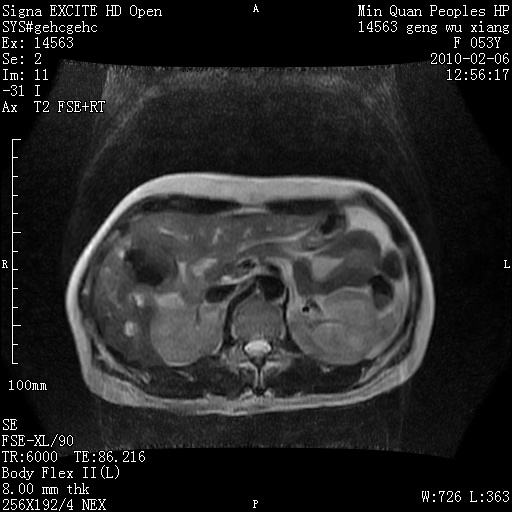

标题: MRI2762:胆道梗阻原因?

f,53y,全身黄染多日。

高位胆道梗阻 胆管癌可能性大

支持 高位胆道梗阻 胆管癌可能性大。